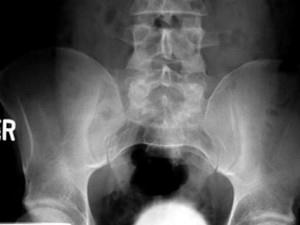

问题 女,38岁,腰背和右侧骶髂关节痛,请结合图像,选出最可能的诊断 ( )

选项 A、骨巨细胞瘤 B、骨髓瘤 C、类风湿关节炎 D、右髂骨结核 E、化脓性关节炎

答案 D